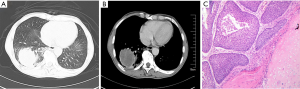

A male patient aged 65 years old who was receiving treatment for membranous nephropathy (MN) for ten months was referred and hospitalized in our hospital because of cough and expectoration. He had a history of bubble urine for one year before hospitalization. Ten months ago, he suffered from fatigue and weight loss, so he consulted at other hospital and underwent urinalysis which revealed proteinuria 3(+) with urinary occult blood positive and normal renal function, his level of proteinuria on successive check-ups was over 3.5 g/day. His serum albumin level decreased to 2.4 g/dL (normal range, 4.0–5.5 g/dL). His chest computed tomography (CT) scan was negative. Subsequently, renal biopsy was performed and histopathological findings was characteristic for MN. During his ten-month therapy for MN, his urinalysis and serum chemistry data showed that the proteinuria, hypoalbuminemia and hypercholesterolemia did not improve. He was a smoker of 20 cigarettes/day for 15 years. He did not drink alcohol, or use intravenous drugs. His family history, psycho-social history and genetic information were unremarkable. On examination, his respiratory frequency was 18 breaths/min, heart rate was 90 beats/min, blood pressure was 106/62 mmHg, body temperature was 36.9 °C and his oxygen saturation was 100% on room air. Chest examination revealed nothing remarkable and edema of the lower limbs was notable. On admission, we arranged chest CT scan for him, which revealed a tumor of 5 cm in diameter at right lower lobe without enlarged lymph nodes (Figure 1A,B). CT-guided percutaneous needle aspiration (PTNA) was performed and histopathology revealed squamous carcinoma (Figure 1C). The patient underwent right lower lobectomy, which revealed a neoplastic mass with a diameter of 5 cm. Histopathology confirmed the diagnosis and the tumor was classified as T3N2M0 (stage IIIA). Postoperatively, the patient received docetaxel 120 mg day 1 plus nedaplatin 100 mg day 1 chemotherapy for four cycles. And his proteinuria disappeared, his serum albumin level increased to 5.5 g/dL. His membranous nephropathy got completely remission. But he denied further therapy on lung cancer, and fifteen months after surgery, the patient died because of relapse of cancer and accompanied deterioration of MN. The timeline picture of the patient was shown in Figure 2.